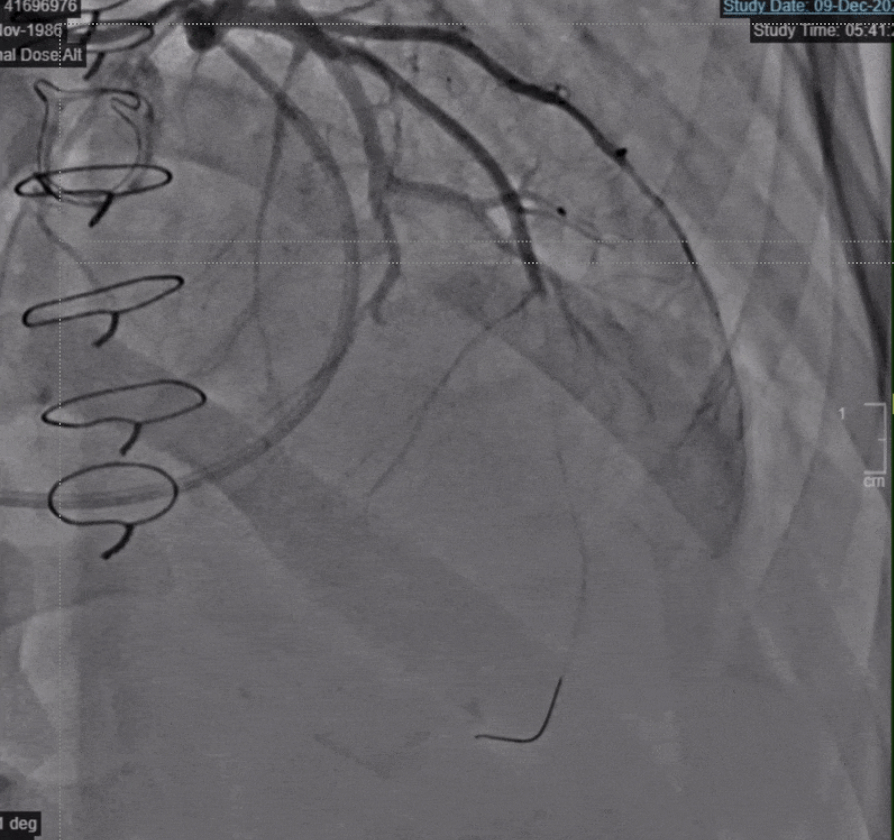

A 38 year old male with a history of bioprosthetic AVR presented initially with palpitations. He was found to be in atrial fibrillation with rapid ventricular response. He subsequently developed sudden severe sub-sternal chest pain radiating to his left shoulder with new ST-elevations in the anteroseptal, anterolateral, and inferior leads on ECG. Emergent coronary angiogram showed acute embolic occlusion of the mid left anterior descending (LAD) and distal left circumflex arteries. Thrombectomy and Balloon Angioplasty were attempted unsuccessfully and an intra-aortic balloon pump (IABP) was placed. Ultimately the Cardiogenic Shock Team was activated, and deliberated endovascular vs surgical approaches. Patient was emergently taken to the OR for LAD thrombectomy, LV thrombectomy, a possible single-vessel coronary artery bypass graft (CABG) to the LAD, possible LAA closure, and a redo surgical AVR. This surgical intervention was ultimately successful.